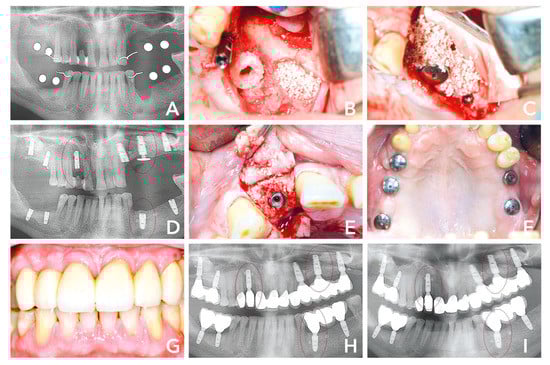

3.2. Case 2

A 50-year-old male patient presented with multiple chronic inflammation at teeth #24, #25 and #34, endodontically treated #16 and hopeless tooth #12. The patient’s treatment options were reviewed prior to his consent to strategic extraction and implant placement. He was advised that a regenerative procedure would be necessary due to the advanced bone loss in region #12, #24–26, #35–37. His preference was an implant fixed restoration in a single-staged approach. The treatment plan was bone augmentation including sinus floor elevation in the second quadrant and implant placement in region #12, #16, #18, #24, #26, #28, #35, #37, #46, and #48. After extraction (Figure 3A,B), three of the sites (#12, #24-25 and #34) were measured with the trephine from the maxgraft® bonering surgical kit (botiss biomaterials, Zossen, Germany) 7 mm in diameter. Accordingly, all of the sites were planned to be treated with 7-mm bone ring (maxgraft® bonering, botiss biomaterials, Zossen, Germany). Tooth 12 showed palatal and buccal bone loss (Figure 2C,D). The site was prepared according to surgical protocol and the graft was fixated with a dental implant (Ankylos Implant, Dentsply Sirona, York). The posterior maxilla in the second quadrant was also treated with immediate implant placement (#24), a 7-mm bone ring fixated with a dental implant (#26) and external sinus floor elevation including implant placement (#28) (Figure 2B) and covered with a bovine bone substitute (cerabone®, botiss biomaterials, Berlin) and a collagen membrane (Jason® membrane, botiss biomaterials, Berlin) in order to prevent resorption and soft tissue inclusion (Figure 2C). The mandible was treated with a cylindrical bone block after preparing the site with a trephine and planator to create a uniform recipient site. Dental implants at #37, #46 and #47 were placed simultaneously. Eight months after surgery, the radiological image indicated well integrated bone grafts and dental implants (Figure 2D). At that time, the re-entry was performed and healing abutments integrated in order to give shape to gingiva. The area showed hard and soft tissue maturation revealing what appeared to be an osseointegrated implant; both clinically and radiographically with complete regeneration of the buccal and palatal bone (Figure 2D,E). Five weeks after re-entry, the soft tissues seemed healthy and final prosthesis were integrated (Figure 2F). Twenty-one months after surgery, the soft tissue situation and the prosthetics looked good and the patient was satisfied with the clinical outcome (Figure 2G). The 14-months post-operative radiological image showed stable implants and bone grafts (Figure 2H). The 36 months image still showed similar results (Figure 2I).

Figure 3. (A) Initial situation 6 weeks after extraction of teeth #12, #24-25 and #34. (B) Second quadrant: implant placement #28, sinus floor elevation and bone augmenation with a 7-mm bone ring block and immediate implant placement #26. (C) Sinus cavity filled with bovine bone substiute and covered with a collagene membrane. (D) Radiological control 8 months after surgery with stable bone around the shouders of the implants. (E) After opening the flap, the graft seemed to be well integrated. (F) Five weeks after re-entry and 9 months after initial surgery healthy soft tissues was observable. (G) Prosthtetic restoration in place. (H) Radiological control 14 months after surgery, (I) compared to 36 months, showed hard tissue maturation and stable dental implants.